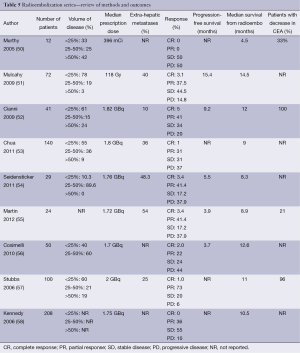

For small hepatocellular carcinomas, the results of RFA approach those of surgical resection with respect to recurrence, time to progression, and overall survival. For colorectal liver metastases, multiple retrospective case matched comparisons as well as meta-analyses are available, which compare surgical resection to RFA (6-8). An increased incidence of recurrence in the treated lesion (5-13%), decreased time to progression, and decreased median survival (1-year, –85%; 3-year, –36%, 5-year, –24%) are reported in patients undergoing RFA compared to surgical resection (7). In well-selected patients with 3 or fewer lesions less than 3 cm in diameter, 5-year survivals of up to 33% are reported (9). In patients who are not surgical candidates, RFA remains a valuable tool. It is increasingly used in conjunction with surgical resection to increase the number of surgical candidates. A study by Livraghi in 2003 demonstrated that RFA followed by incomplete ablation or recurrence in the ablative bed did not negatively affect subsequent surgical resection (10). The most important factor for local recurrence after RFA is tumor size, and larger lesions are at higher risk for local failure (Table 1).

In most reports, prior to DEBIRI chemoembolization, patients had undergone previous chemotherapy and failed at least one line of chemotherapy, with some having failed two or three regimens of chemotherapy. In general, patients tolerate DEBIRI well with the most common adverse event being the post-embolization syndrome. Abdominal pain, occasionally severe, is reported in 40-63% of patients. Hypertension is also frequently reported but is most often transient and related to pain. Aliberti reported results in 82 patients who failed initial lines of chemotherapy with response to DEBIRI of 78% at three months, progression free survival of 8 months and median survival of 25 months (42). These results are similar to those reported by Martin with response at 6 and 12 months of 66% and 75%, and progression free and overall survivals of 11 and 19 months, respectively (43). Other reports and meta-analyses report response to treatment in 18-78% of patients with median survival rates of 15-25 months (44). Patients failing only first line chemotherapy exhibit better overall response and survival compared to patients having failed multiple lines of chemotherapy. In a randomized trial comparing DEBIRI to 5-fluorouracil (5-FU)/leucovorin/irinotecan in patients failing first lines of chemotherapy, time to progression and overall survival favored DEBIRI at 7 and 22 versus 4 and 16 months, respectively (44). Toxicity including neutropenia, diarrhea, and mucositis were less frequent in the DEBIRI group (44). Both standard chemoembolization and DEBIRI have been reported to downstage up to 20% of patients to surgical resectability (45) (Table 4).

The risks of this procedure include constitutional symptoms and abdominal pain, gastric/duodenal ulcer for which prophylactic proton pump inhibitors are initiated, and radiation induced liver injury. Results of radioemblization are shown in Table 5.

Full table

Candidates for liver SBRT should have a sufficient performance status (ECOG 0-1) and liver function and no extrahepatic disease. The uninvolved liver volume should be 700 mL or greater (64). Based on the volume of disease, patient comorbidities, baseline liver function, and performance status, the multidisciplinary team can begin to make treatment recommendations for liver-directed therapy. For diffuse disease, the embolization procedures may be appropriate therapy. Although outcomes appear similar in chemo- and radio-embolization, it is important to recognize that the volume of disease in the available literature may be inconsistent. Likewise, most SBRT series allow for larger lesions than RFA despite having apparently similar outcomes (Table 6).